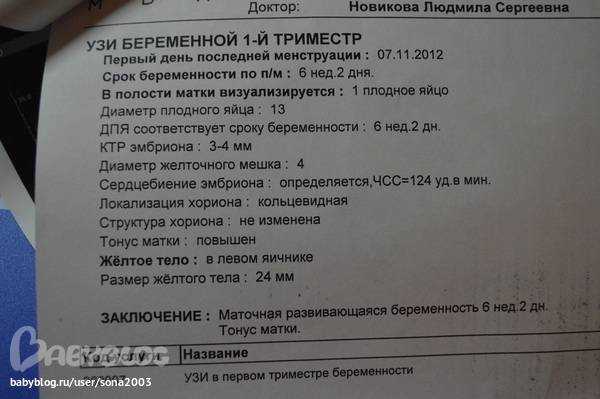

Узи при беременности на раннем сроке.

Информативность узи на ранних сроках беременности

Следите за регулярностью УЗИ, так как мониторинг состояния матки в динамике позволяет выявить возможные отклонения на ранних сроках.